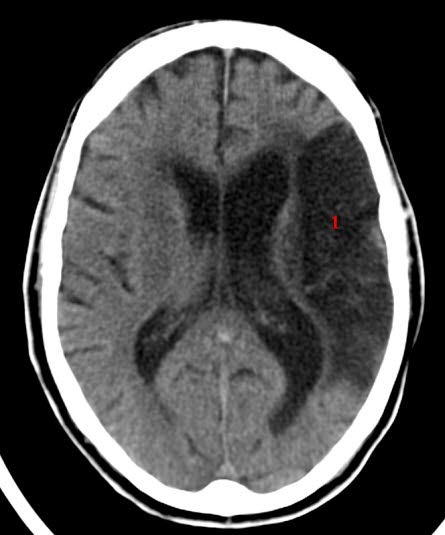

Cerebralt infarkt (CT)Venøs blodpropp i hjernen - cerebral venetrombose - er en trombose i en av hjernens større vener. Det er en spesiell form for hjerneslag. Tilstanden bør mistenkes hos enhver pasient som presenterer seg med alvorlig hodepine og brekninger uten annen underliggende sykdom.

Diagnosen kan være vanskelig å stille fordi den er så sjelden at man ikke tenker på den. Diagnosen krever bildeundersøkelser av hodet, CT og/eller MR, eventuelt med bildeopptak etter innsprøyting av kontrast i blodårer.